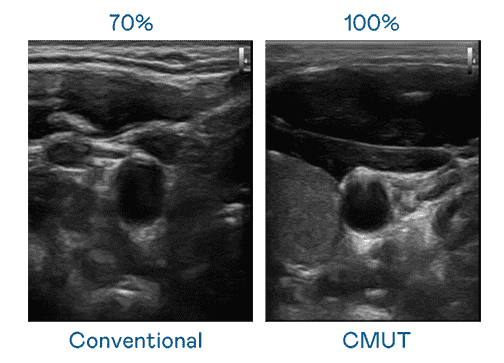

CMUT 技术是一种用电容式微机电元件来产生超音波讯号的技术。。。与传统 PZT 压电式技术相比,,,,CMUT 频宽增加 30%,,,,更宽频的超音波讯号让影像解析度大幅提升,,,是实现高影像品质医疗超音波扫描、、、、促进精准医疗发展的关键技术。。。。

超音波影像的解析度高低,,,,首先取决于探头能发出的讯号频宽。。。万利 CMUT 可提供高清晰的超音波讯号,,,提供高频宽、、高灵敏度、、、影像纹理细节更高的超音波影像,,,协助医护人员缩短影像判读时间及利用精准的医疗影像进行诊断。。。。